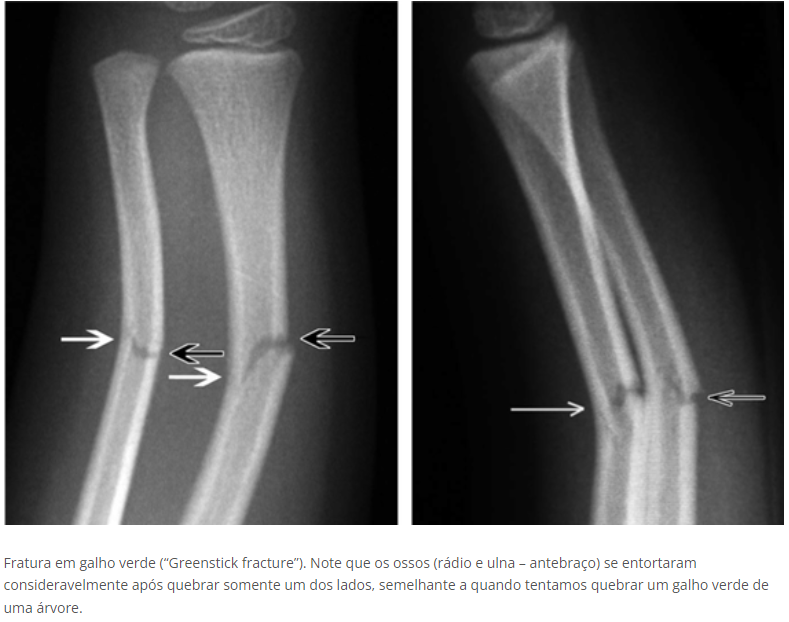

Galho verde

• Típica de criança

• Fratura incompleta

• Principalmente no antebraço na área da metáfise

• Devido ao periosteo espesso, há ruputura da cortical de um lado e preservação da cortical oposta